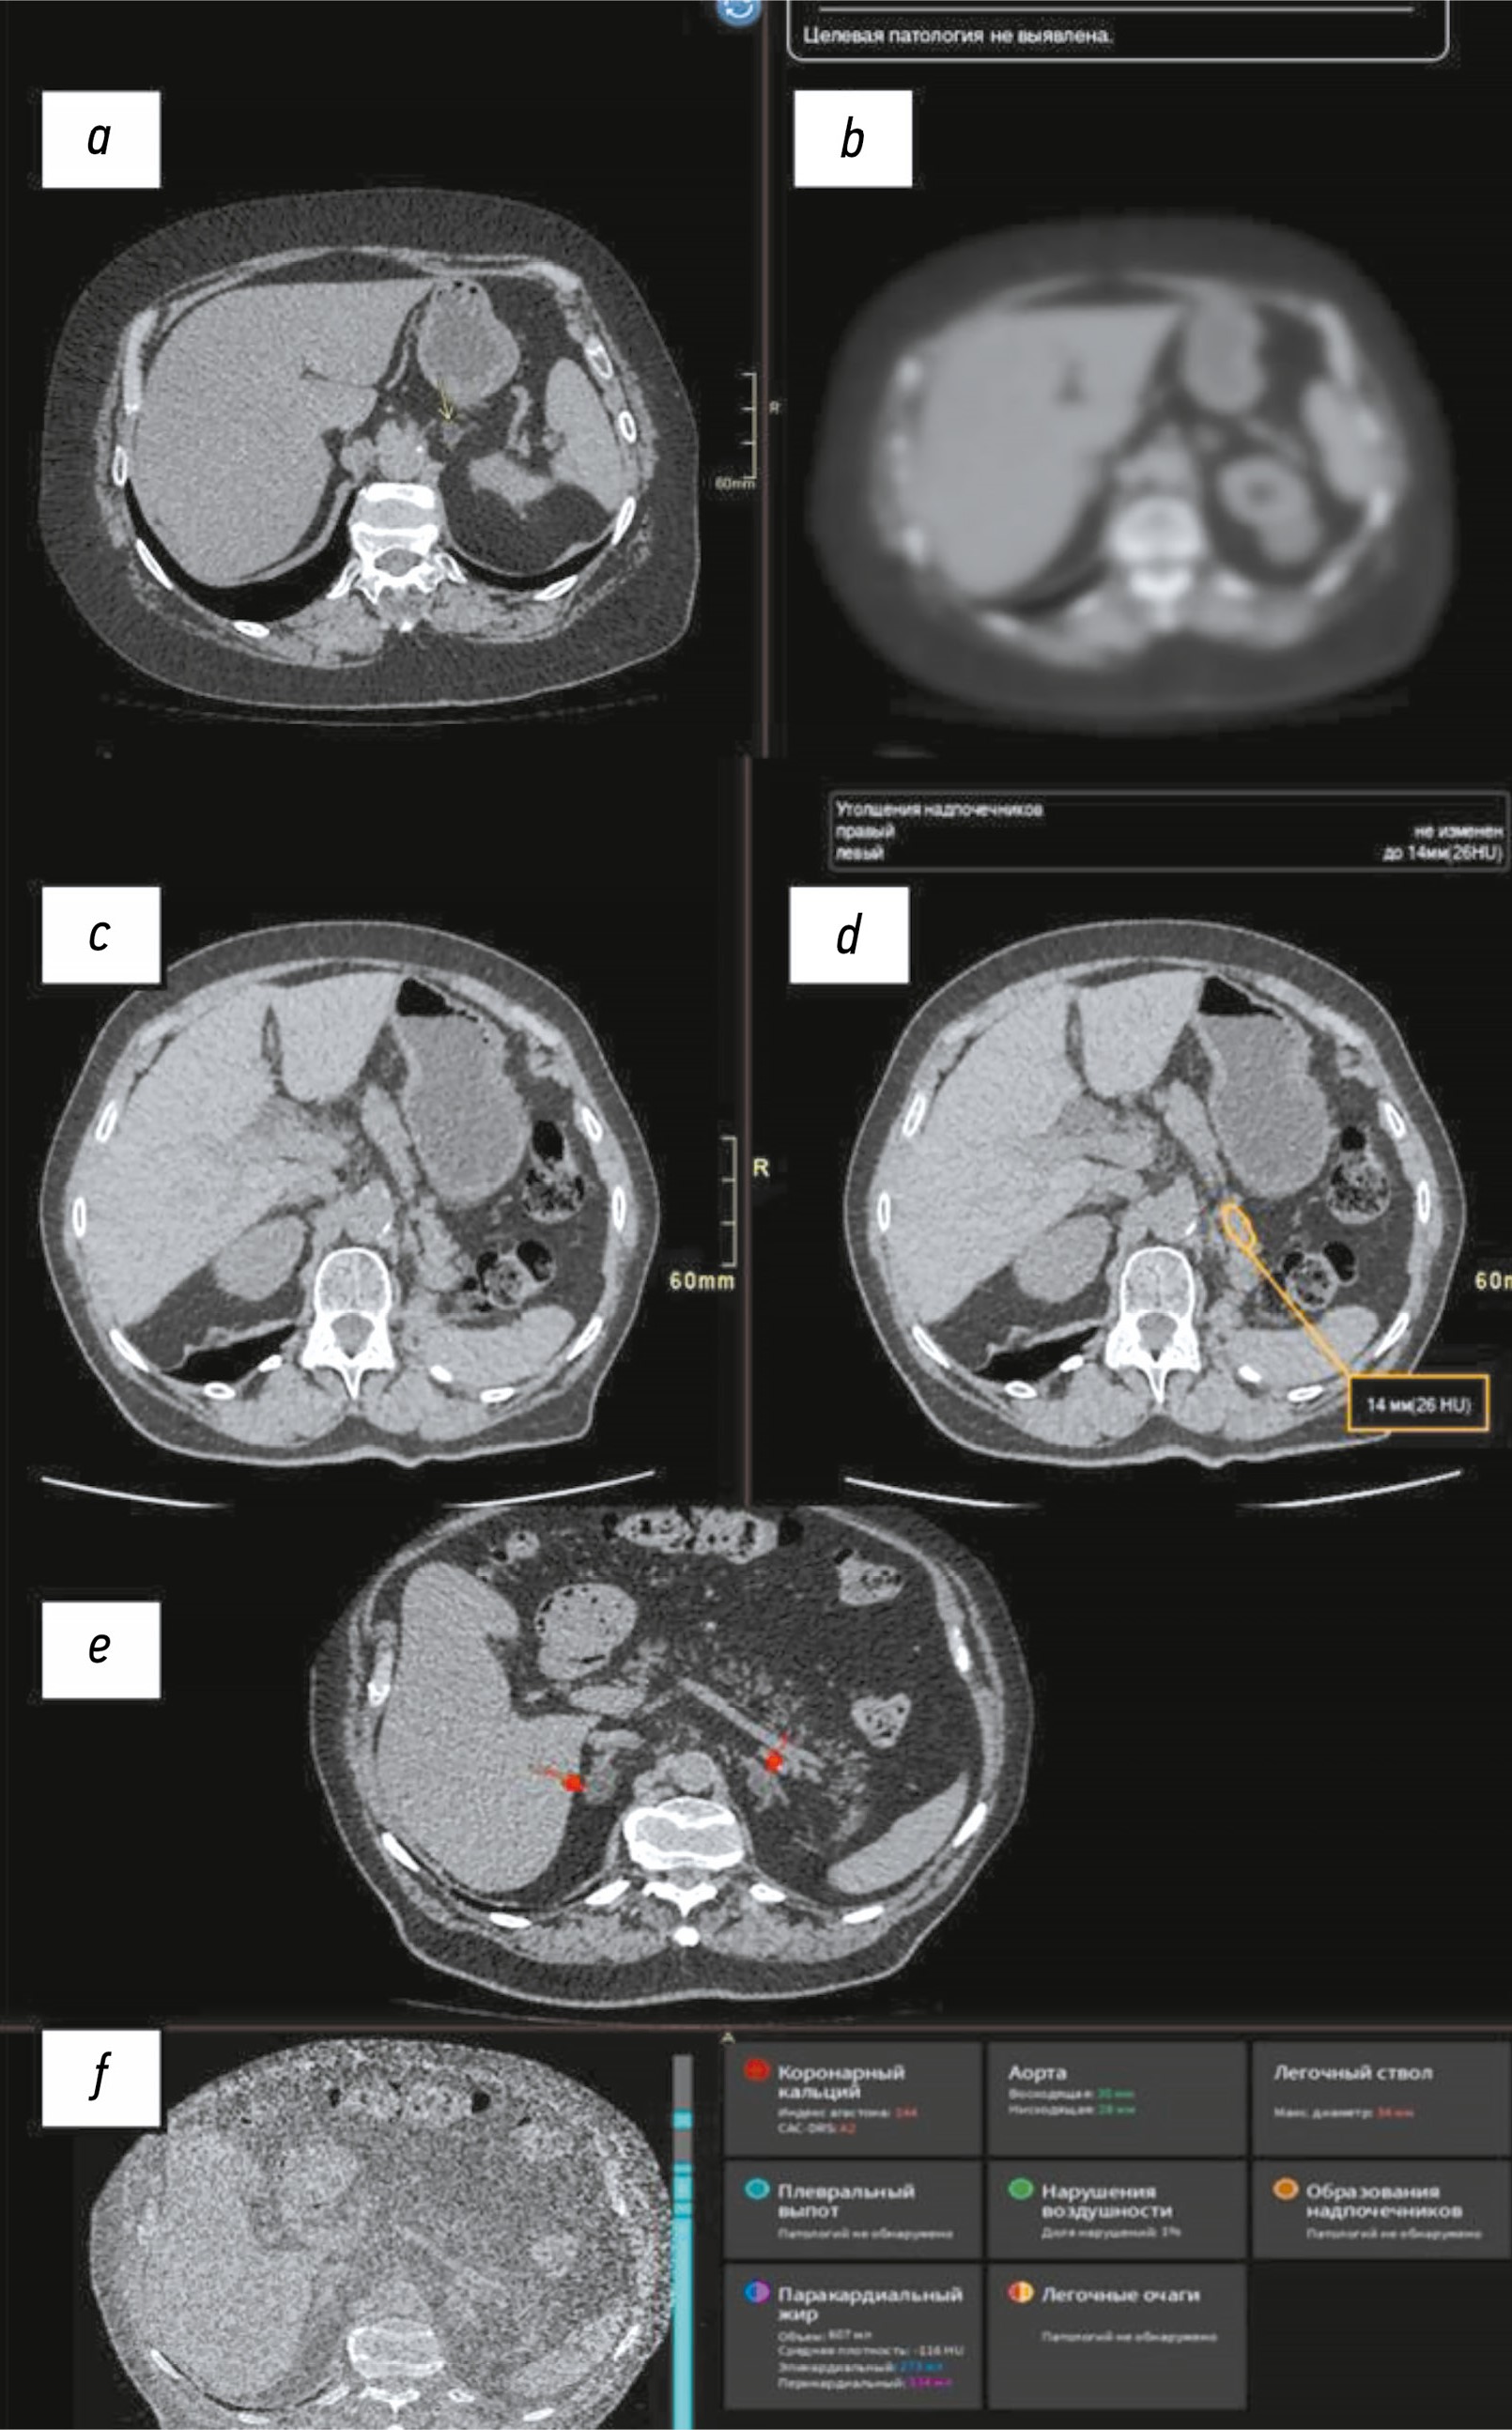

Примеры некорректного работы ИИ-сервисов при выявлении новообразований надпочечников представлены на рис. 4.

Рис. 4. Примеры некорректного срабатывания сервисов на основе искусственного интеллекта при выявлении новообразований надпочечников: a — пропущенное новообразование надпочечника (жёлтая стрелка); b — пропуск сервисом на основе искусственного интеллекта новообразования левого надпочечника (ложноотрицательный результат); c — результаты компьютерной томографии органов брюшной полости; d — оконтуривание хвоста поджелудочной железы в качестве новообразования надпочечника (ложноположительный результат); e — невыявленные новообразования надпочечников (красные стрелки); f — пропуск комплексным сервисом на основе искусственного интеллекта новообразований надпочечников по данным компьютерной томографии органов грудной клетки в лёгочном режиме (ложноотрицательный результат).